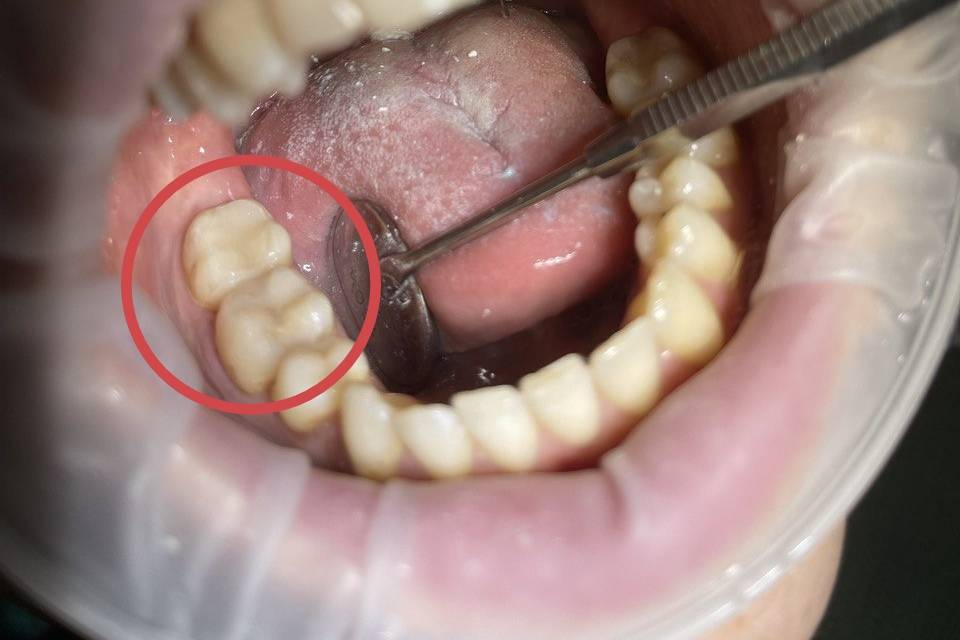

Профессиональная гигиена с использованием технологии AirFlow включает в себя: - снятие пигментированного налета с применением порошкового метода AirFlow, при котором из специальногохэнди - бластера под давлением подается профессиональный мелкодисперсный порошок - полировка зубов профессиональной щеткой и пастой - покрытие зубов фторосодержащим препаратом - Использование технологии Air Flow позволяет удалить налет от чая, кофе, так называемый "налет курильщика". С твердыми зубными отложениями (зубной камень) AirFlow не справится |